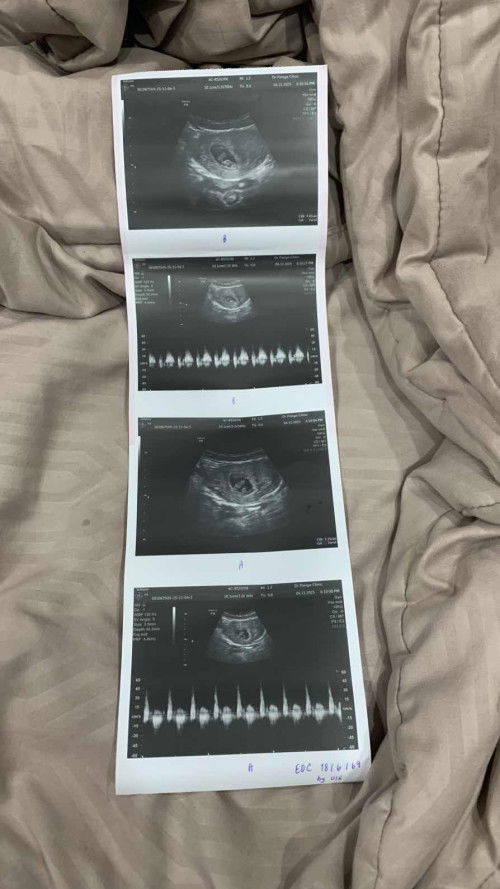

เมื่อวานไปหาหมอซาวด์ท้องเห็นไม่ชัดคุณหมอเลยใช่วิธีสอด เห็นชัด ได้ยินเสียงหัวใจ 6สัปดาห์ ได้ยาบำรุงเลือดมาทานหลังจากกลับเราไปเดินห้างต่อปรากฏว่าเลือดออกเยอะมากต้องใส่ผ้าอนามัยเปลี่ยนไป2แผ่น แผ่นที่3เช้ามา ก็ยังมีเลือดแต่ไม่เยอะเท่าเมื่อวาน ท้องแรกจิตใจกังวลกลัวไปหมด ตอนนี้ใส่แผ่นที่4 ถ้าหยุดไหลก็พอให้สบายใจถ้าไม่หยุดไหลต้องไปโรงพยาบาล แม่ๆท่านไหนเป้นไหมคะ น้องจะเป้นอะไรไหม หรือเพราะเราเดินเยอะ🥺🥺 #ขอบคณสำหรับคำตอบล่วงหน้านะคะ #ท้องแรก #คอมเม้นท์มาหน่อยคะ